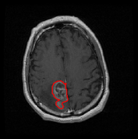

We first introduce a method for connecting the output of a CNN to an ACM, yielding a model for the precise delineation of lesions, to which we refer as Deep Active Lesion Segmentation (DALS) (Figure 4). We then go further to introduce a truly unified framework (Figure 5) that bridges the gap between ACMs and CNNs by leveraging a novel, automatically differentiable level-set ACM with trainable parameters that allows for back-propagation of gradients and can be end-to-end trained along with a backbone CNN from scratch, without any CNN pre-training. The ACM is initialized directly by the CNN and utilizes an energy functional that is locally-tunable by the backbone CNN, through 2D feature maps. Thus, our work overcomes the big hurdle of fully automating the powerful ACM approach to image segmentation. We have applied our proposed framework to the task of building segmentation in aerial images (Figure 6).

Deep Active Lesion Segmentation

[45]: Lesion segmentation is an important problem in computer-assisted diagnosis that remains challenging due to the prevalence of low contrast, irregular boundaries that are unamenable to shape priors. We introduce Deep Active Lesion Segmentation (DALS), a fully automated segmentation framework that leverages the powerful nonlinear feature extraction abilities of FCNs and the precise boundary delineation abilities of ACMs. Our DALS framework benefits from an improved level-set ACM formulation with a per-pixel-parameterized energy functional and a novel multiscale encoder-decoder CNN that learns an initialization probability map along with parameter maps for the ACM. We evaluate our lesion segmentation model on a new Multiorgan Lesion Segmentation (MLS) dataset that contains images of various organs, including brain, liver, and lung, across different imaging modalities—MR and CT. Our results demonstrate favorable performance compared to competing methods, especially for small training datasets. -